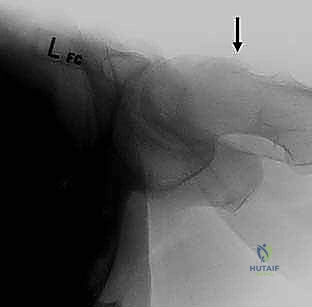

- انحشار الكامة (Cam Impingement): يحدث عندما لا يكون رأس عظمة الفخذ كروياً بشكل مثالي. وجود نتوء عظمي إضافي على شكل "كامة" يؤدي إلى احتكاكه بحواف التجويف عند ثني الفخذ، مما يقشر الغضروف ويمزق الشفا.

5. معالجة التشوهات (إعادة التشكيل العظمي - Osteochondroplasty):

* في حالة انحشار الكامة (Cam): يستخدم الدكتور هطيف أدوات دقيقة لإزالة النتوء العظمي الزائد من رأس وعنق الفخذ، وإعادة الشكل الكروي المثالي له، مما يسمح بحركة سلسة دون احتكاك.